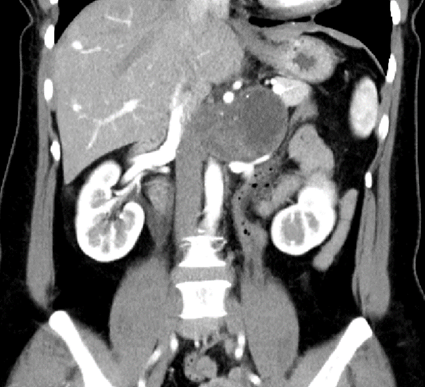

l CT:腹膜后偏左囊实性团块,边界清,增强实性部分不均匀轻中度强化,5.3*7.8*5.9cm,临近组织受推压。

7. 分离顺序:上极→内侧→下极→外侧→向中心。肿瘤上极见多支穿支血管进入肿瘤,其中包括一支粗大血管进入肾脏,复习术前影像,考虑可能为挤压变形的肾动脉,遂保留。

a) 术前细致的影像学评估,判断累及的器官及大血管走向,做到胸中有数。本例虽为神经鞘瘤,增强CT强化不明显 ,但较大肿瘤压迫导致回流不佳形成较多侧支循环,分离时应轻柔精细操作,及时电凝、夹闭或缝扎血管减少出血。肿瘤占位作用也导致正常血管移位(例如上极的肾动脉、肿瘤前上方的肠系膜上动脉),需严格保护。术前需反复阅片。